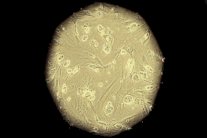

| حين يتعرض سمك الزرد لقطع في الحبل الشوكي فإن جسراً من الخلايا الداعمة يبدأ في التكون بين الطرفين |

وتبين للباحثين من خلال الدراسة التي راقبوا فيها سمك الزرد أنه حين يتعرض لقطع في الحبل الشوكي، فإن جسراً من الخلايا الداعمة يبدأ في التكون بين الطرفين.